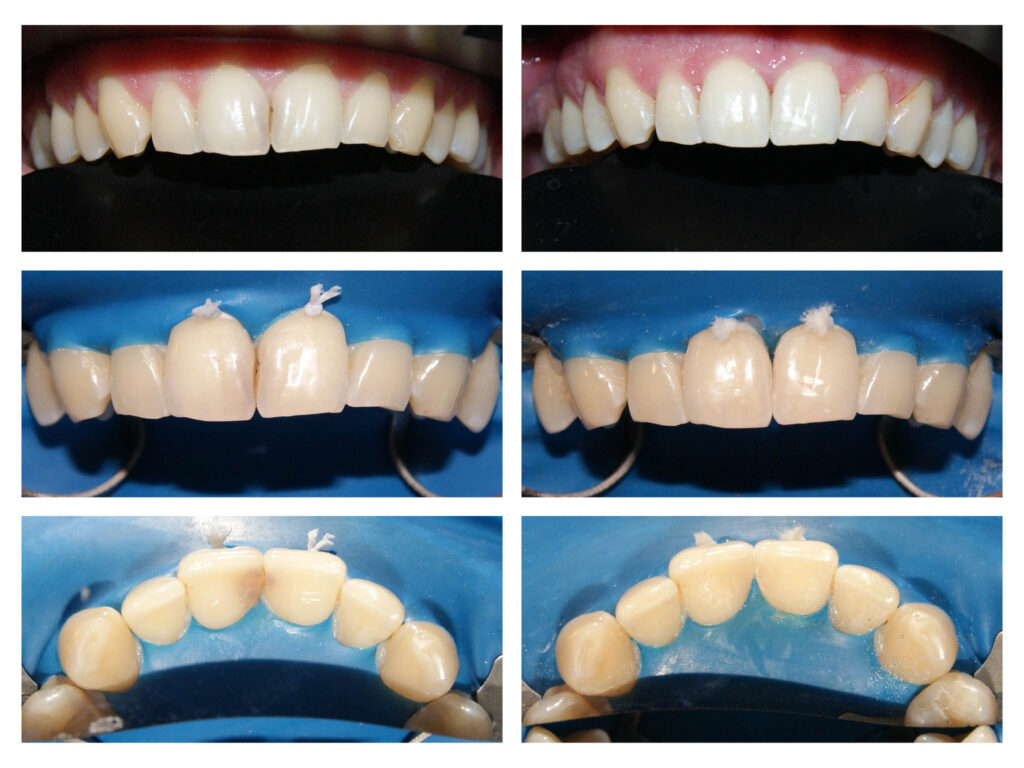

Lucrare protetică din Zirconiu stratificat- integrare estetică- praguri minim invazive pe dinți tineri, vitali – gingii sănătoase

Protezarea fixă a incisivului central superior cu lucrarea din zirconiu stratificat